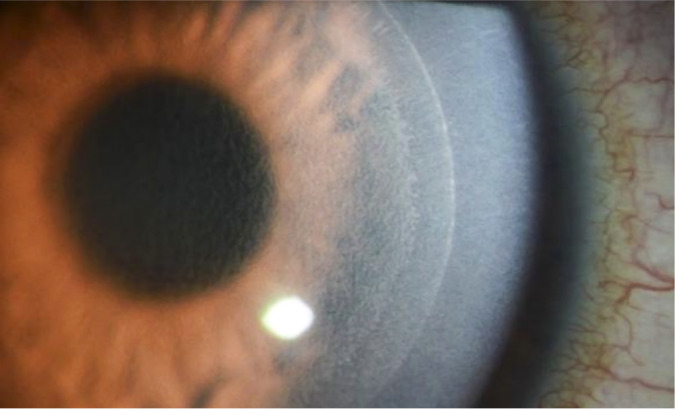

Complications in patients who have undergone laser refractive surgery.

Abstract Image